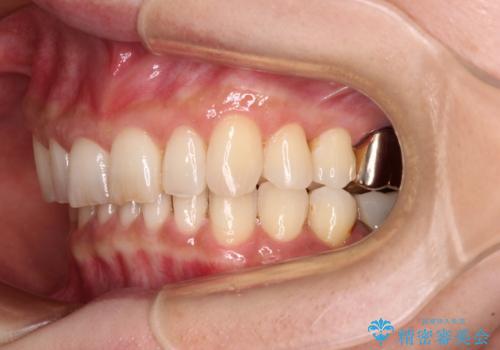

デコボコの歯とむし歯 インビザライン矯正治療とむし歯治療

- 奥歯が咬めないくらいに痛いとのことで来院された患者様です。

痛みの強い歯は、歯髄組織が強い炎症を起こしており、神経を取り除く必要であったため、速やかに根管治療を行いました。

その後、オールセラミッククラウンにて補綴治療を行う予定でしたが、処置した歯以外にも治療が必要と思われる歯があったり、デコボコした歯列も気になるとのことで、患者様希望によりインビザラインにてマウスピース矯正を行うこととしました。

まずは矯正治療前に必要なむし歯処置を行い、その後矯正治療を行ってから、最後にオールセラミッククラウンなどで補綴治療を行うこととしました。

咬合力が非常に強く、全体的に歯が擦り減っている状態であったので、理想的な咬み合わせを達成することは難しく、また咬合力が強い方のマウスピース矯正は、思い通りに動かないことがあるため、ワイヤー矯正の方が望ましいように思えました。